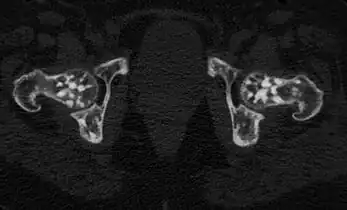

Osteopoikilosis of the hips on CT. -

The radiographic appearance of osteopoikilosis on an X-ray is characterized by a pattern of numerous white densities of similar size spread throughout all the bones. This is a systemic condition. It must be differentiated from blastic metastasis, which can also present radiographically as white densities interspersed throughout bone. Blastic metastasis tends to present with larger and more irregular densities in less of a uniform pattern. Another differentiating factor is age, with blastic metastasis mostly affecting older people, and osteopoikilosis being found in people 20 years of age and younger.

In terms of the diagnosis Osteopoikilosis is radiographically evaluated via the presence of multiple symmetrical circular sclerotic opacities [2]

The distribution is variable, though it does not tend to affect the ribs, spine, or skull.[3]